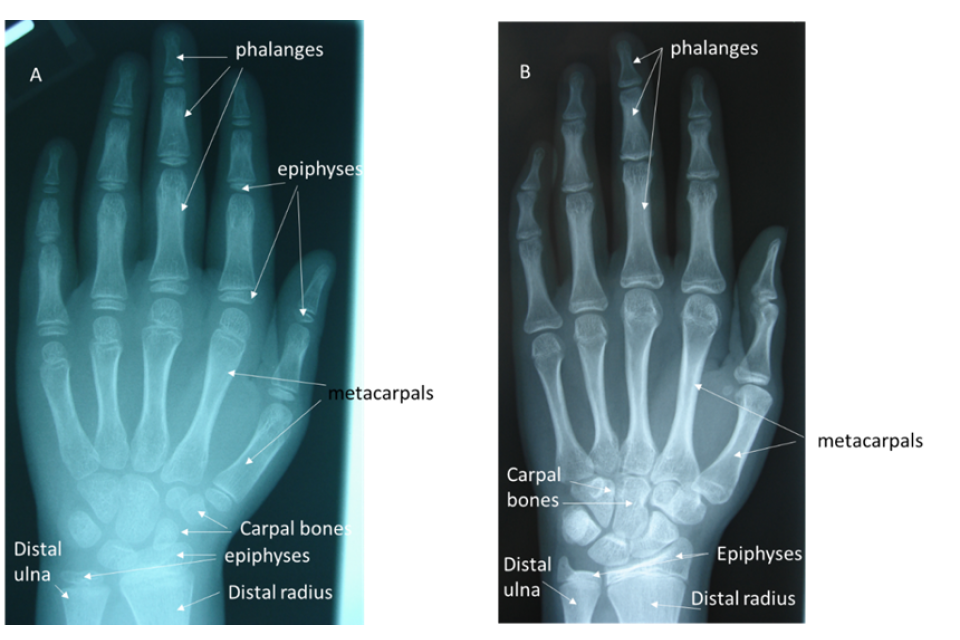

4.40. Use of a radiograph of the hand/wrist to assess age is based primarily on maturation of the small bones in the wrist (carpals), the long bones in the palm (metacarpals) and fingers (phalanges), and the wrist end of the two long bones of the forearm – the radius and ulna (see Figure 4). While convention states that the left hand/wrist should be used, research has shown that either side of the body can be used interchangeably (Hackman and Black, 2012).

4.41. Maturation takes the form of changes to the shape and relative size of the bones, and the degree of fusion between the epiphysis (at the end of the bone) and the diaphysis (the bone shaft). The epiphysis and the diaphysis generally develop separately before fusing once maturity is reached (see Figure 4 which shows separate epiphyses in the image of the immature hand and wrist (A) but which are fused to the diaphysis in the image of the mature hand (B)).

4.42. These visible changes occur over a well-documented age range and can be correlated with chronological age using a reference dataset which allows comparison between the appearance of the bones seen in the radiograph and the appearance that would be expected at known ages.

4.43. The last bone to mature is the distal radius where fusion is complete by around 16 years in females and 17 to 18 years in males.

Figure 4: Radiographs of the hand and wrist of a female aged 10 years (A) and a female aged 17 years female (B) showing the bones and the epiphyses, the ends of long bones that initially grow separately from the shaft.

Radiographs described above.